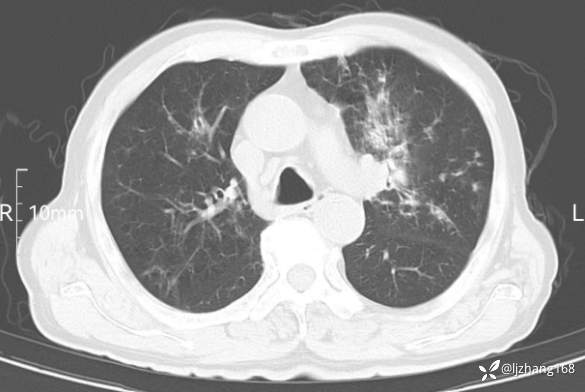

辅助检查:胸部CT:双肺肺气肿,间质性病变,血气分析:PH 7.413, PCO2 29.2mmHg, PO2,81.8mmHg,乳酸 3.3mmol/1,剩余碱-4.0mmol/1,HC03 18.8mmol/1。全血超敏C反应蛋白:超敏C反应蛋白 135.60 mg/L、 白细胞 14x19^9/L,中性粒细胞11.6x10^9/L。